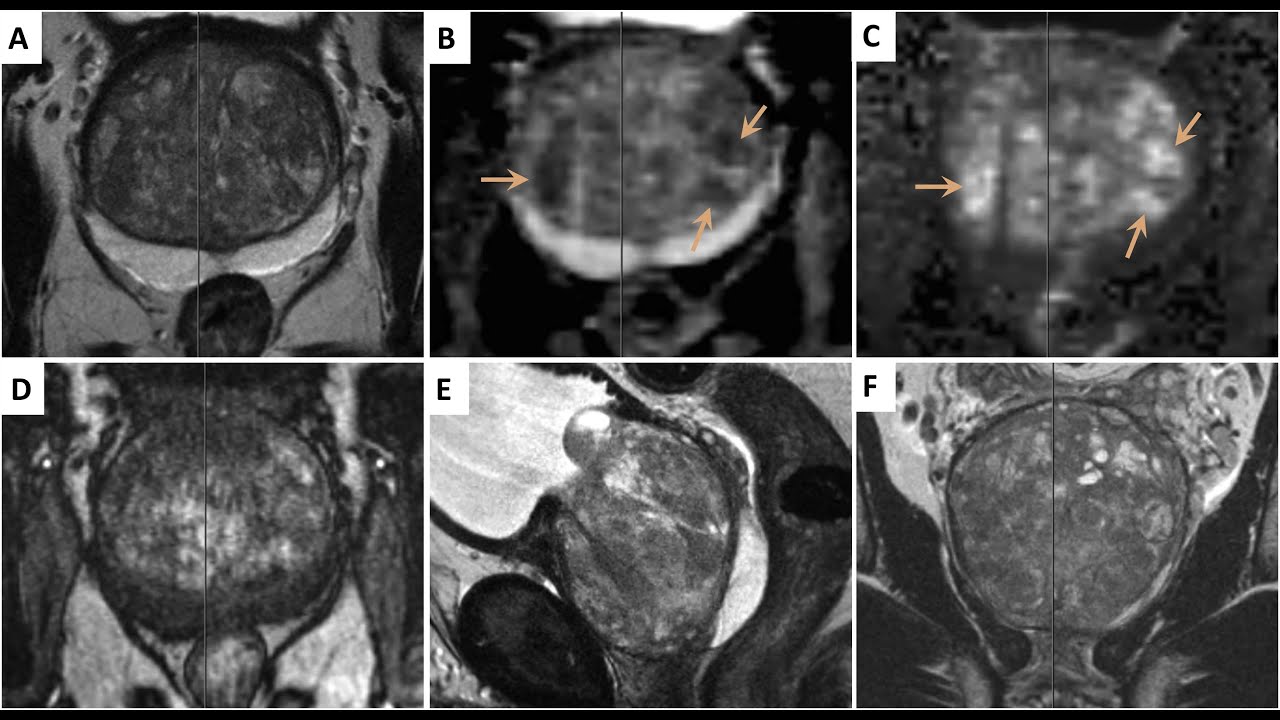

MR-TRUS füzyon, prostat kanseri tanısında kullanılan gelişmiş bir biyopsi tekniğidir. Manyetik Rezonans (MR) görüntüleme ile elde edilen detaylı prostat görüntüleri, Transrektal Ultrasonografi (TRUS) ile birleştirilerek hedef odaklı biyopsi yapılmasını sağlar. Bu yöntem, klasik biyopsi tekniklerine göre daha hassas bir tanı süreci sunar.

- MR görüntülemede şüpheli lezyonların tespit edilmesi

- Hedefe yönelik biyopsi olanağı: Sadece şüpheli alanlardan biyopsi alınmasını sağlayarak daha doğru tanı konulmasını destekler.